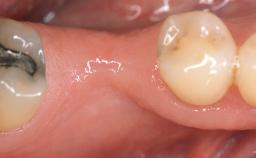

A 30-year-old woman was referred by her general dentist for evaluation of an esthetic complication related to previous implant treatment for congenitally missing maxillary lateral incisors. The patient’s chief complaint was the inadequate esthetic appearance of her smile. The case demonstrates the use of a combined approach to achieve optimal results. Two different flap designs - a tunnel technique and a coronally advanced flap - are employed based on the surgical objectives for the affected site.

Prosthesis Type FDP